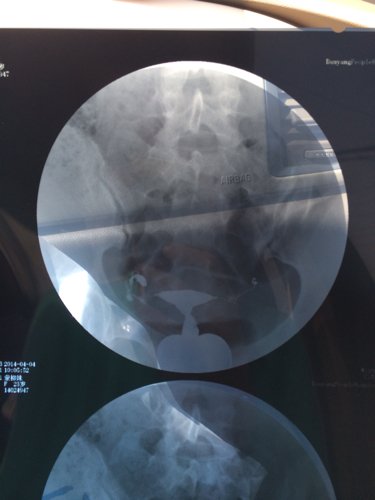

您好,医生。昨天我去做了一个子宫输卵管造影,结果检查所见子宫形态无明显异常。双侧输卵管伞部显影,双侧输卵管呈迂曲柔软的条状影。24小时后摄片示,造影剂在盆腔内积聚,弥散不良。检查结论双侧输卵管伞部碘油积聚,弥散不良,提示双侧输卵管伞部梗阻。请问医生我该怎么治疗,还有没有机会会人工受孕怀个健康宝宝呢?